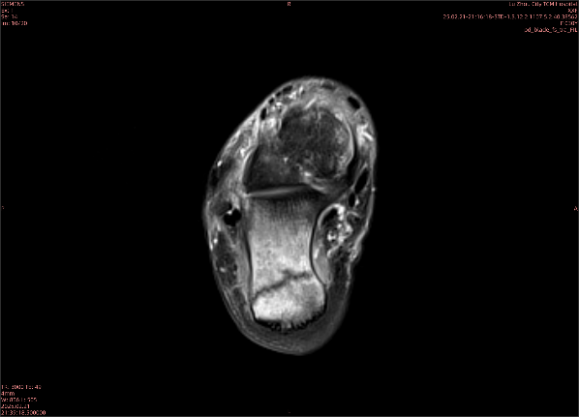

舉例圖像

圖1

圖2

專業(yè)解釋看不懂沒關(guān)系,大家看圖1和圖2就可以了,這是同一個(gè)患者跟骨的磁共振和CT圖像,圖1的紅色箭頭指示的黑線就是磁共振圖像顯示的骨折線,一目了然。而對(duì)比圖2的CT圖像上并未顯示異常。